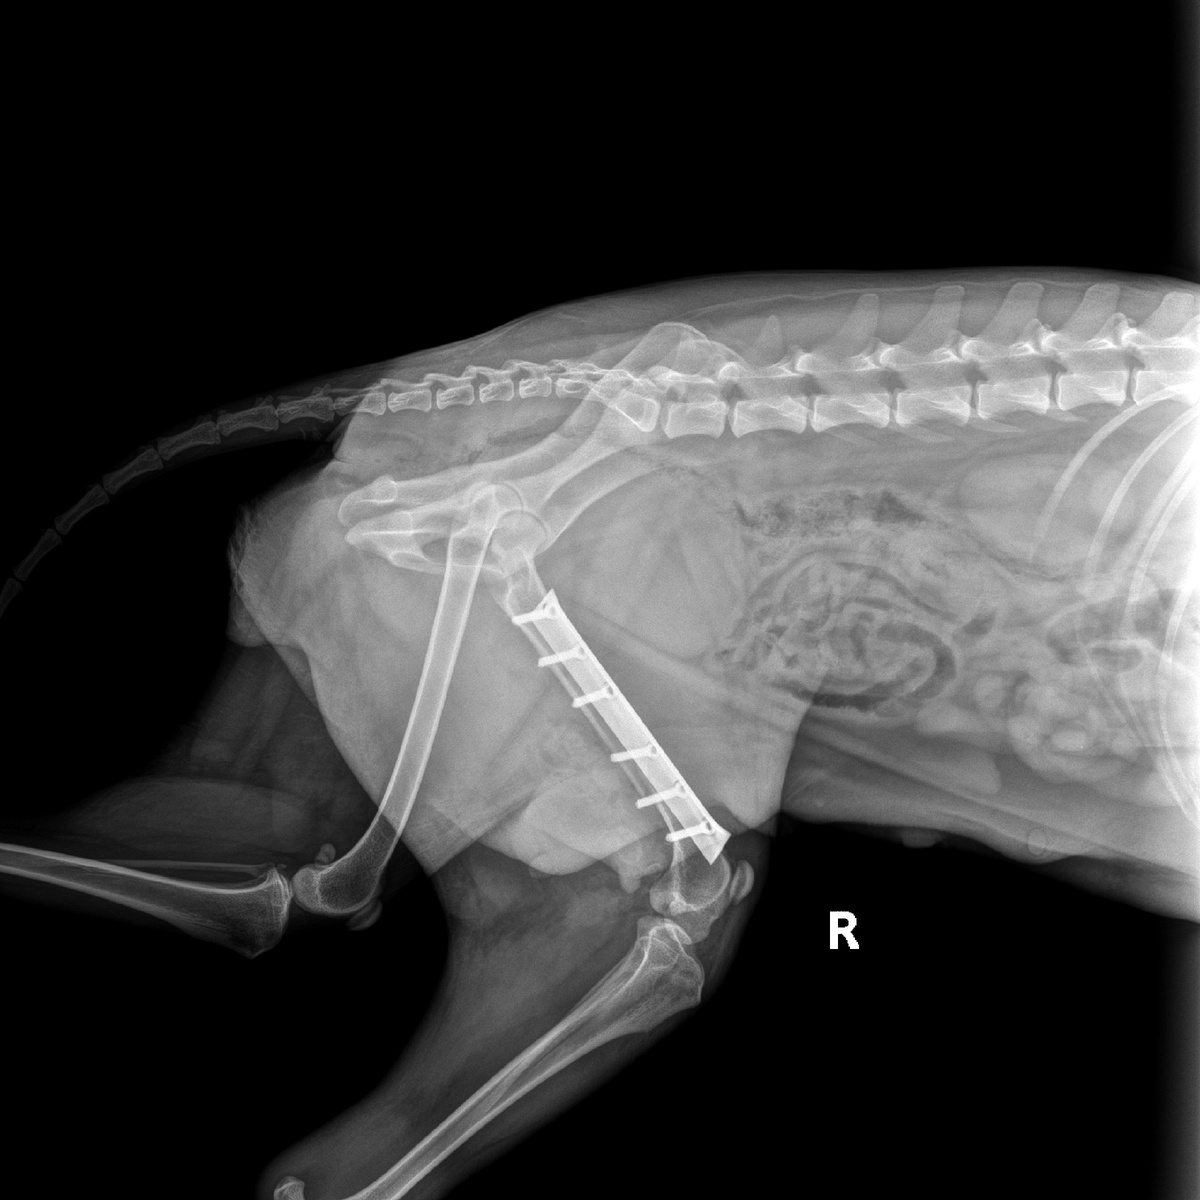

Мотютак (зовут эту собаку,) прооперировали, с диагнозом перелом тазовой кости, а у неё щенки которым по 1.5 мес. Очень жалко смотреть на то как ей больно, но малышей кормить нужно 😞, вот и прочность клетки, прутья разворотила, беды наделала... Кто может не проходите мимо поста, операция с долгом по Боцману 26.000 руб,оплатила 20.000 руб.Помощь приюту всегда актуальна. Финансово можно помочь переводом на наши реквизиты: ❗Карта ПСБ: 2200030502292973 ✅Привязана к номеру +7 (949) 417-86-70 БИК: 044525555 Корр. счет: 30101810400000000555 ИНН/КПП: 7744000912/997950001

Мотютак (зовут эту собаку,) прооперировали, с диагнозом перелом тазовой кости, а у неё щенки которым по 1.5 мес.

Очень жалко смотреть на то как ей больно, но малышей кормить нужно 😞, вот и прочность клетки, прутья разворотила, беды наделала...